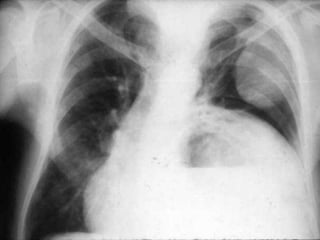

CRITERIOS DE EVALUACIONRX. TX.  Pulmones desde ápex hasta senos costo diafragmáticos  Pulmones y corazón sin rotación.  10 pares de costillas.  Sombra área de la tráquea centrada sobre la columna.  Balance en los contrastes de la imagen (exposición adecuada).

INTERPRETACION  Revisar estructuras óseas.  Partes blandas.  Espacios intercostales.  Parénquima pulmonar  Nivel de los senos costodiafragmaticos.  Neumatización.  Trama alveolo-pulmonar  Silueta cardiaca  Cayado aórtico.